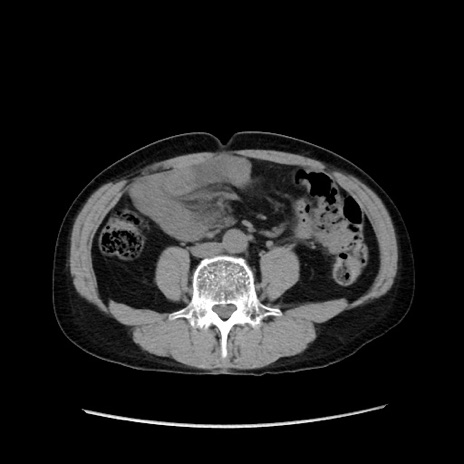

症例37(横断像)

【症例】40歳代 男性

【主訴】腹痛

【現病歴】4時間ほど前に電車に乗車中に臍部上より腹痛出現。徐々に増悪し起立困難となり、救急外来受診。生ものは数日食べていない。今朝お雑煮を食べた。

【身体所見】BT 36.8℃、BP 117/84mmHg、HR 91/min、SpO2 97%、苦悶様、腹部:臍上部広範囲圧痛あり、反跳痛±

【データ】WBC 8100、CRP 0.03